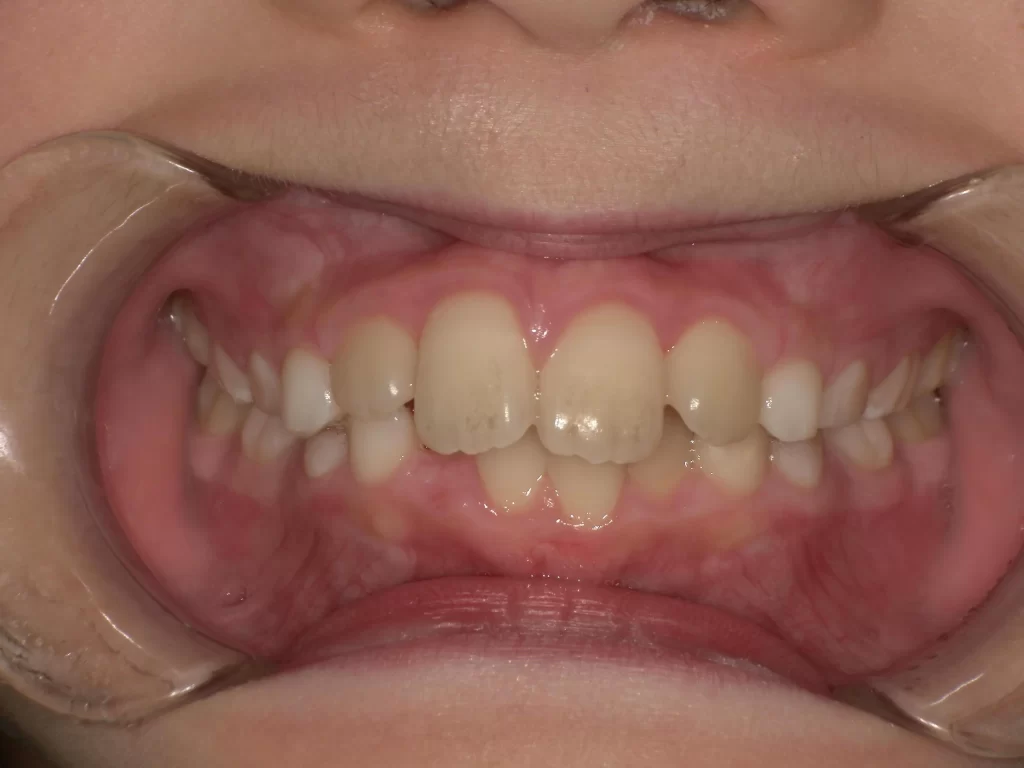

症例②:内側に入った前歯を1本だけ治したい

【期間:3.5ヶ月 / 費用:約8万円】

「上の前歯が1本だけ内側に入り込んでいる」というケースです。金属ワイヤーを使用し、超短期間で改善しました。

▼ 治療前(Before)

▼ 治療中(金属ワイヤーを使用)

▼ 治療後(After)

- お悩み: 前歯1本のねじれ・反対咬合

- 治療法: 部分矯正(金属ワイヤー)

- 期間: わずか3.5ヶ月

- 費用: 8万円(税別)

- 結果: 10万円以下の費用かつ、3ヶ月ちょっとという短期間で、コンプレックスだった前歯が正しい位置に並びました。